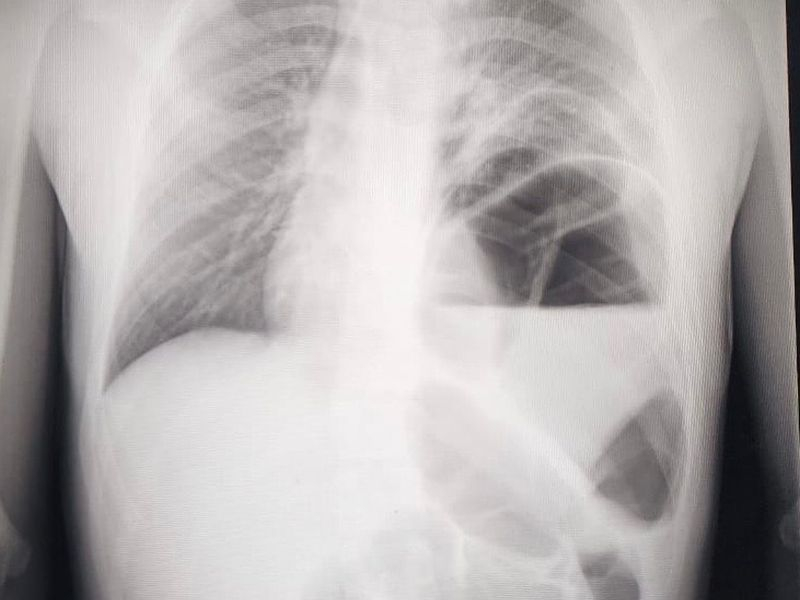

4 февраля в воронежской больнице №2 имени Федяевского сообщили об успешных операциях у двух детей. У малышей наблюдался редкий порок развития, именуемый диафрагмальной грыжей. К тому же подобный парный случай ранее не был описан ни в одном медицинском учебнике, но о нем наслышаны все. Диафрагмальная грыжа заключается в перемещении органов из брюшной полости (кишечник, желудок и т.д.) в грудную полость через естественное или патологическое отверстие в диафрагме (ложные). Также перемещение происходит путем выпячивания истонченного участка диафрагмы (истинные).

Дети поступили в больницу, когда у них нарастали симптомы сердечно-легочной недостаточности. Поэтому врачи начали оперировать маленьких пациентов в экстренном порядке. Медики увидели, что в грудную клетку переместились желудок, селезенка, поперечная ободочная кишка, сальник и участок тонкого кишечника. В итоге малыши были успешно прооперированы, у них был устранен дефект диафрагмы.